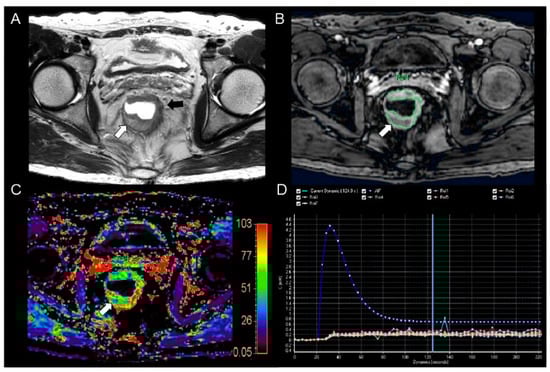

Figure 3.

MR images from a 54−year−old man with pathologically proven moderately differentiated rectal adenocarcinoma. (A) The T2−weighted axial image shows eccentric wall thickening (black arrow) in the lower rectum. Focal high signal intensity is seen (white arrow) in the posterior portion of the tumor. The focal lesion was histologically revealed to be mucin accumulation in the tumor. (B) The post−contrast axial 3−dimensional spoiled gradient echo image shows a heterogeneous enhancement in the corresponding tumor. Relatively poor enhancement is seen in the mucin accumulation site (arrow). (C) The color-coded Ktrans map shows a wide range of colors from purple to red in the corresponding tumor. Mixed blue and purple colors are seen in the mucin accumulated portion (arrow). The calculated mean Ktrans was 0.063 min−1. (D) The concentration time curve shows a plot of arterial input function (AIF, blue line), which was implemented automatically with the population−based data and seven plots from the consecutive seven regions of interest (ROIs−1 to 7) in the whole tumor (different colored lines).